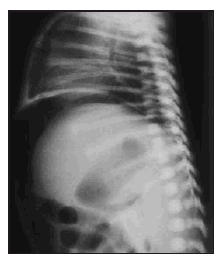

Se trata de un recién nacido a término mujer, primera hija de padres jóvenes y sanos, procedente de embarazo controlado. La madre recibió tratamiento con diazepam oral por ansiedad los 4 días previos al parto. Parto vaginal y eutócico a las 38 semanas de edad gestacional. Test de Apgar de 9 al minuto y 10 a los 5 minutos. Peso al nacimiento: 2.730 g. Las primeras 48 h de vida permanece en la maternidad, asintomática, recibiendo lactancia materna exclusiva, con tolerancia adecuada, realizando varias deposiciones meconiales. El tercer día aparece rechazo de tomas, afectación del estado general, color grisáceo de piel y ligera distensión abdominal. Se solicita analítica sanguínea, obteniendo valores hematocitométricos y bioquímica normal salvo PCR de 68 mg/l. Es ingresada en la unidad de neonatología donde se instaura perfusión hidroelectrolítica, así como antibioticoterapia intravenosa con ampicilina y gentamicina. La gasometría al ingreso muestra una leve acidosis metabólica. En la radiología practicada se aprecia en la proyección anteroposterior (fig. 1) el signo del balón de rugby, así como elevación de ambos hemidiafragmas. En la radiografía lateral (fig. 2) el aire libre perfila el límite del hígado y del diafragma. Otros signos de neumoperitoneo están presentes como es la visualización de la pared de asas intestinales. En las 2 h siguientes la niña presenta deterioro progresivo con incremento de la distensión abdominal, taquicardia y taquipnea que mejoran tras la colocación de sondas nasogástrica y rectal. Se comprueba elevación de la PCR hasta 203 mg/l sin alteraciones significativas en la hematocitometría. Presenta una calcemia de 6,6 mg/dl. El hemocultivo fue negativo. Se hace el diagnóstico de perforación intestinal, añadiendo clindamicina al tratamiento y se traslada al Servicio de Cirugía Pediátrica del Hospital General Yagüe de Burgos, donde se practica laparotomía. Los hallazgos operatorios muestran una peritonitis biliar por perforación en la primera porción del duodeno, lineal y de bordes netos, de la totalidad de la cara anterior. Se procede al cierre en 2 planos. Se establece sondaje gastroyeyunal a través de gastrotomía de Stamm y drenajes de Penrose a nivel parietocólico bilateral que se retiran en el quinto día de postoperatorio. A los 12 días se retira la sonda de gastrostomía, siendo dada de alta a la edad de 16 días, asintomática, con excelente tolerancia digestiva. En las revisiones posteriores se constata la absoluta normalidad clínica y nutricional de la paciente.

Figura 1. Gran burbuja aérea abdominal que perfila los límites laterales de la cavidad abdominal y dibuja al ligamento falciforme en hipocondrio derecho, originando con el borde de la columna una imagen oval (signo del balón de rugby).